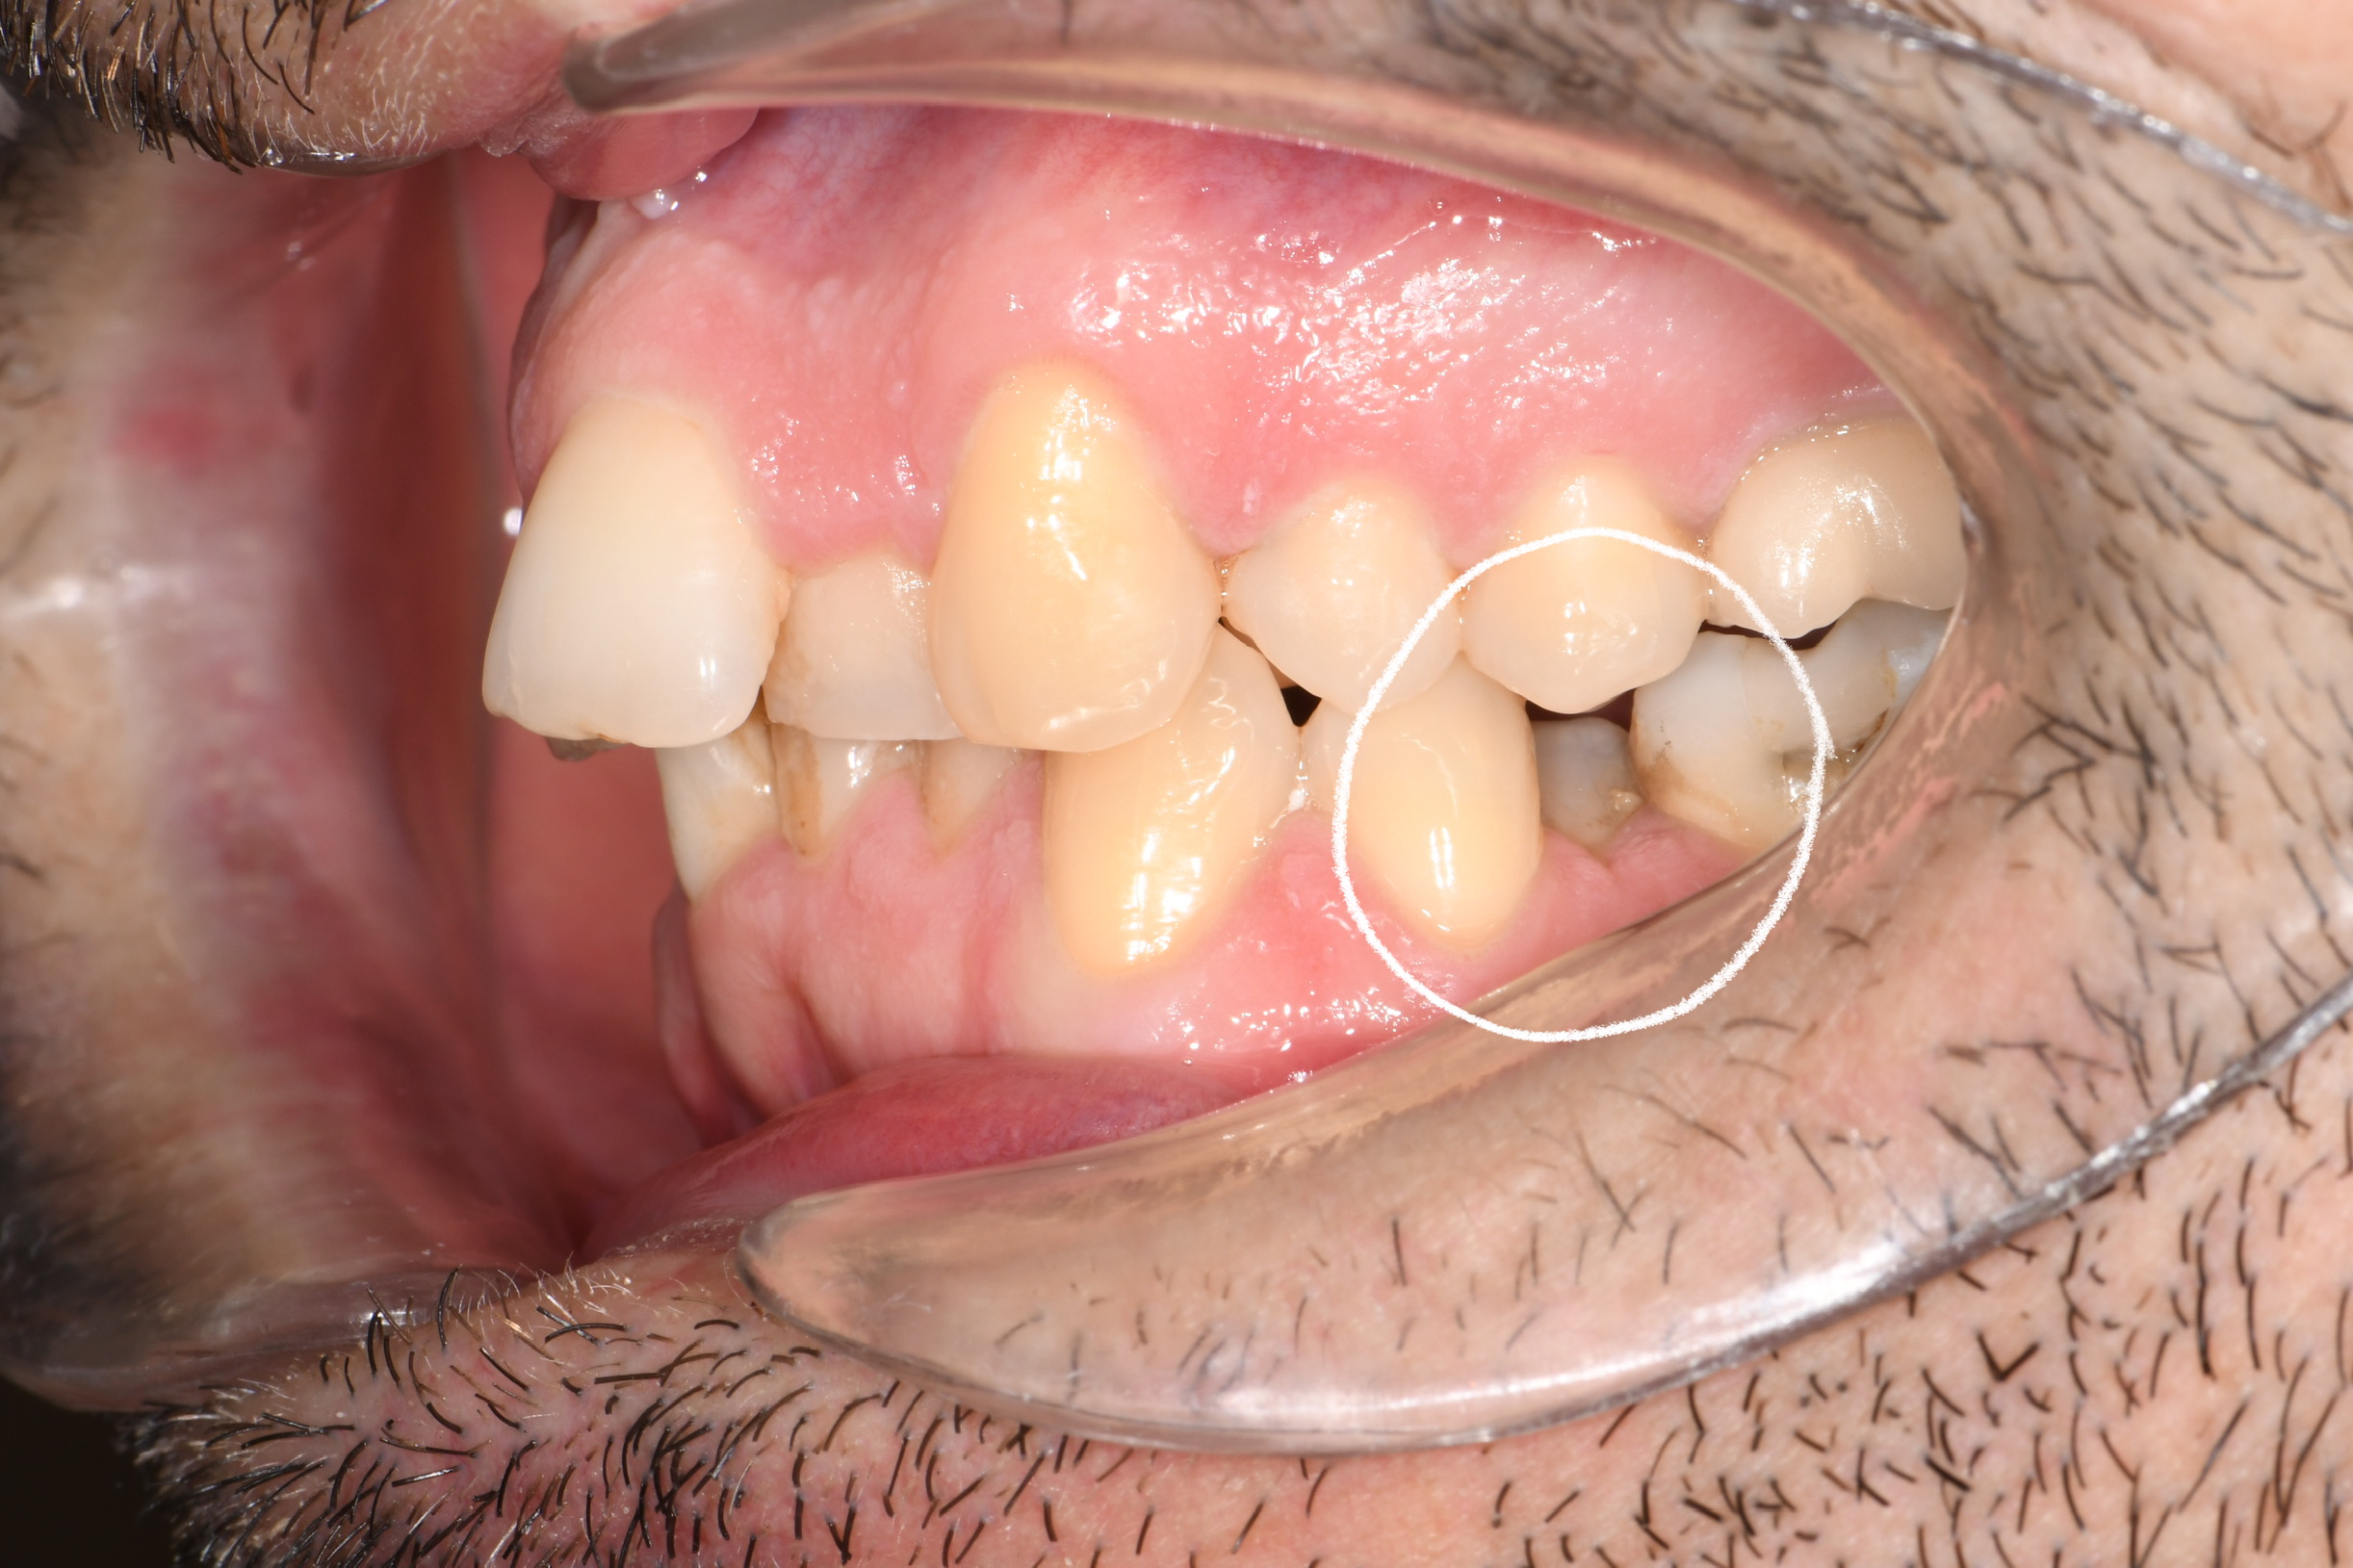

Az elmúlt évekből rengeteg szakmai referenciát tudnánk bemutatni, amelyek különböző fogszabályozási problémákat oldottak meg. Válogatva a több száz esetből, ezen az oldalon olyan képeket, információkat igyekeztünk bemutatni, amelyeknek a segítségével a jövőbeni pácienseinknek azt tudjuk üzenni: A Te fogsorod is lehet gyönyörű!